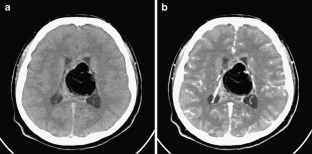

This case involves an 18-year-old man who presented with abnormal behavior, impairment in recent memory, and emotional change. Five years ago, he received five cycles of chemotherapy using cisplatin and ectoposide and 24G of local radiotherapy for clinical diagnosis of suprasellar germinoma in another hospital. The tumor was then completely resolute. Magnetic resonance imaging in our hospital revealed a large fatty mass located primarily in the septum pellucidum and some portions of the corpus callosum; a heterogeneous enhancing tumor was observed in the surrounding area. The second tumor was completely removed. The histological diagnosis was mixed GCTs containing the component of a germinoma and a mature teratoma.

Fig. 4